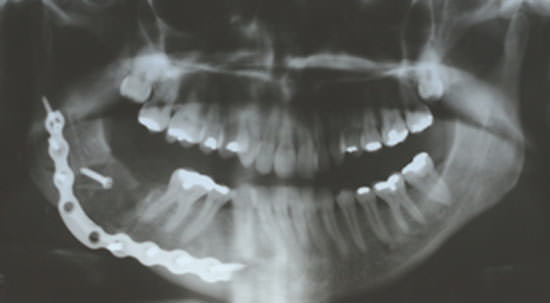

La paciente fue sometida a la remoción de la lesión sobre anestesia general. Fue empleado injerto óseo autógeno de cresta ilíaca que fue fijado con tornillos a través de la vía transcutanea con una placa de reconstrucción de titanio del sistema 2.4 mm respetando el contorno óseo mandibular, (figura 4) instalada por vía intrabucal, finalizando con la sutura de la mucosa, con hilos reabsorvibles.

Figura 4

Examen radiográfico con 15 días de post-operatotio, muestra la placa de reconstrucción respetando el contorno óseo mandibular.